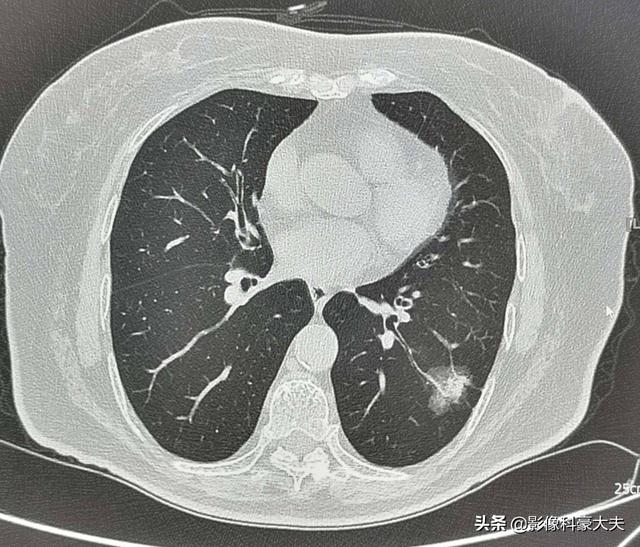

Bei dieser Frau mittleren Alters mit einem 2,2 cm großen Mischmembran-Glasknoten in der linken unteren Lunge handelt es sich beispielsweise um einen Hochrisikoknoten, der in der Tat die klassischen Anzeichen eines Lungenadenokarzinoms aufweist, zu denen gehörenGut ausgeprägter Mattigkeitsschatten mit Gefäßeintritt und Verdickung, bronchiales Insufflationszeichen, distale Pleurabeteiligung, chirurgische Pathologie eines invasiven LungenadenokarzinomsDiese Art von Läsion wird nicht zur Nachsorge empfohlen und sollte zur Abklärung weiter untersucht werden, um eine Metastasierung und eine verzögerte Behandlung zu vermeiden.

Wir müssen jedoch auch erkennen, dass nicht alle Hochrisikoknoten Lungenkrebs sind und dass auch Knoten, die kleiner sind als die oben aufgeführten Hochrisikokriterien, Lungenkrebs sein können! Die Leitlinien sind für uns nur ein Tropfen auf den heißen Stein.